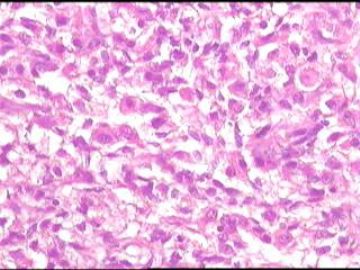

•25岁,女性,停经35周,发现腹腔包块1月余。

•手术所见:右侧卵巢肿瘤,12×8.6×8.0cm大小,表面光滑,内实质似鱼肉样、部分区域胶冻状,伴少许盆腔积水。

• 卵巢肿瘤图3

图3

性索间质来源的肿瘤。

硬化性间质瘤